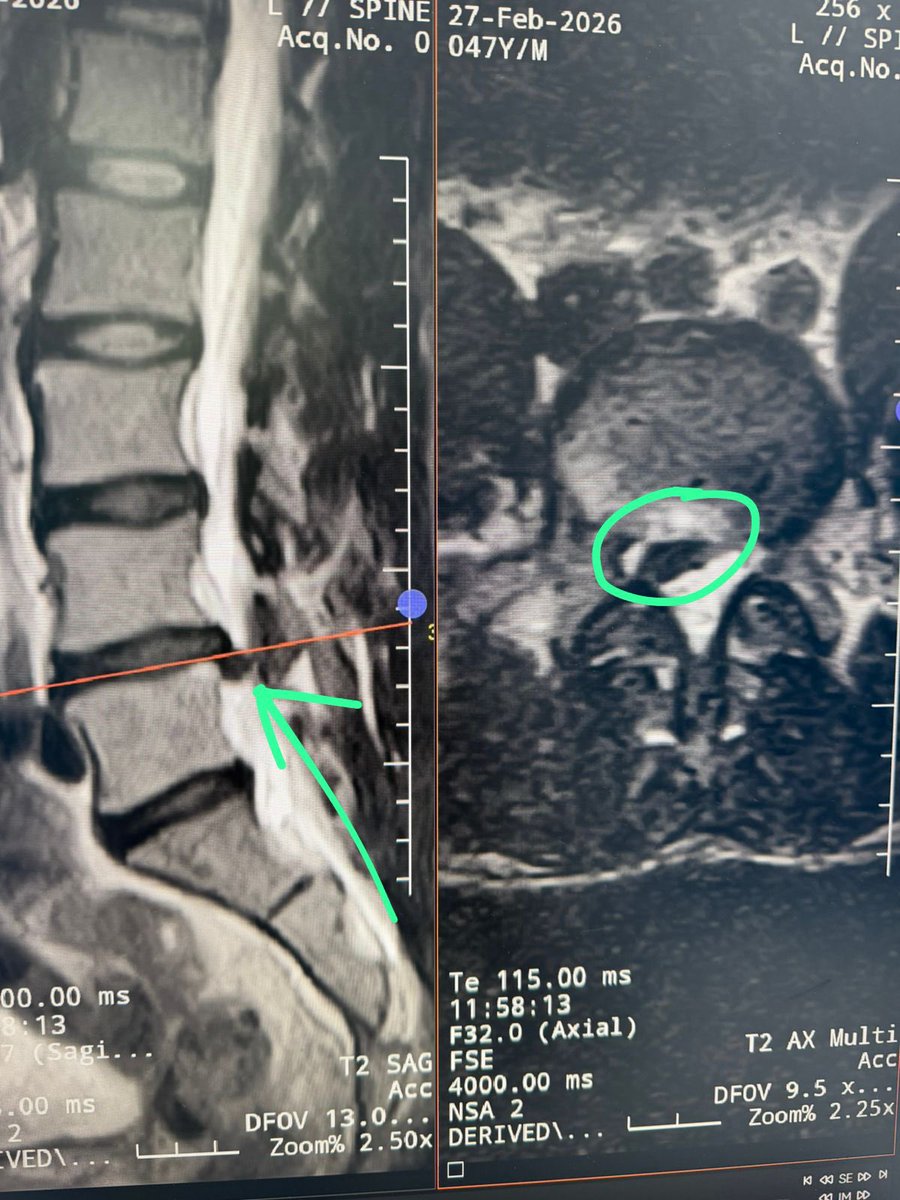

Injured my back in Egypt 🇪🇬 climbing through pyramids , got a steroid shot today in my vertebrae to help with the inflammation and pain! A few months to recover but I’ll be back stronger than ever 💪🏼 the staff at American Hospital in Dubai and @reislin_model_ took good care of me!